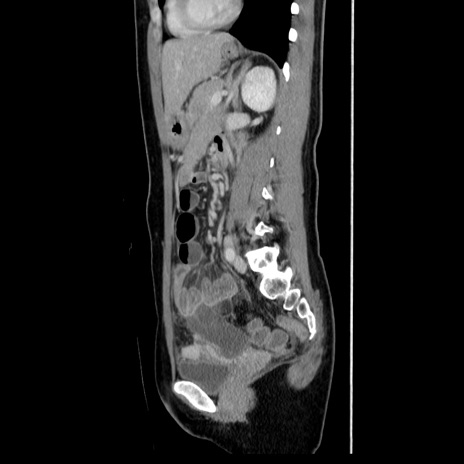

症例39(矢状断像)

【症例】40歳代女性

【主訴】上下腹部痛

【現病歴】2日目から下腹部痛あり。夜間は痛みで眠れなかった。昨日より上腹部痛と下痢が出現。臥位で痛みは軽快したため、休んでいた。本日になって臥位でも立位でも痛みが強くなってきたため救急要請。

【既往歴】子宮内膜症

【身体所見】部:平坦・軟、左上下腹部に圧痛あり、反跳痛あり。

【データ】WBC 21800、CRP 26.78

CT